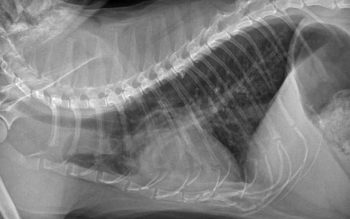

In BAL samples from healthy cats, again, alveolar macrophages are present in large numbers. However, in most studies, feline BAL samples frequently contained large numbers of eosinophils, and they may even be the predominant BAL cell type. A large proportion of neutrophils may also be present in clinically healthy cats. Finer classification of feline lower airway disease is, therefore, challenging. Crudely, our diagnosis must rely on the presence of clinical signs, demonstration of supportive findings, such as radiographic changes and airway cytology, and exclusion of various infectious (or occasionally neoplastic) causes.

However, a variety of clinical presentations may be appreciated; some cats have a mild but persistent cough for months to years, others rarely cough, but show continuous laboured, wheezy breathing, and a minority of cats lead a normal symptom-free life, but suffer intermittent, sudden onset severe respiratory distress, which, in some cases, may be life-threatening. These latter presentations may be the ones that most closely resemble asthma in people. Interestingly, radiographic changes may sometimes be subtle or lacking in this subset of feline patients, supporting a theory dynamic reversible bronchoconstriction is occurring in response to some stimulus.